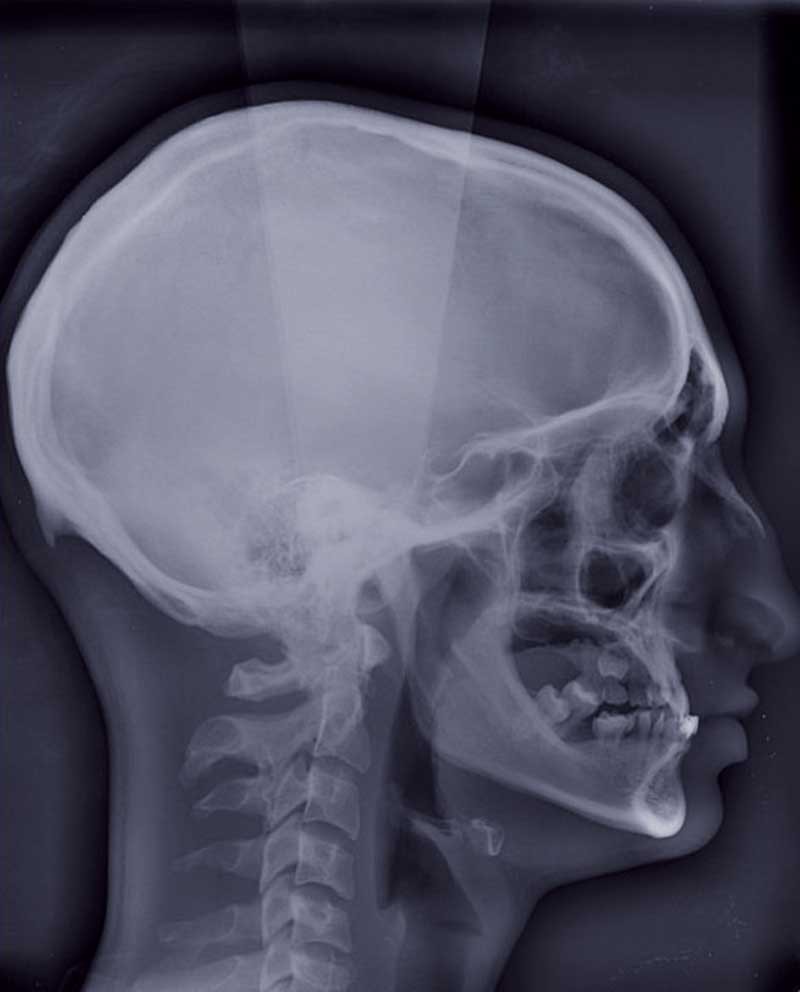

La mandibule est maintenue stable pendant l’examen. Sa position varie selon la typologie du patient. En cas de normo ou d’hyper-divergence, la mandibule est stabilisée en relation centrée (fig. 1).